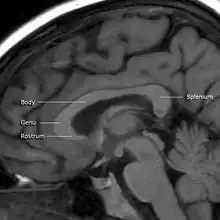

![]() Sagittal section of brain, front part to the left. The corpus callosum can be seen in the center, in light gray | |

A number of separate nerve tracts, classed as subregions of the corpus callosum, connect different parts of the hemispheres. The main ones are known as the genu, the rostrum, the trunk or body, and the splenium.[4]

The corpus callosum has four main parts – individual nerve tracts that connect different parts of the hemispheres. These are the rostrum, the genu, the trunk or body, and the splenium.[4] A narrowed part between the trunk and the splenium is known as the isthmus. Fibres from the trunk and the splenium known together as the tapetum form the roof of each lateral ventricle.[6]

The front part of the corpus callosum, towards the frontal lobes, is called the genu ("knee"). The genu curves downward and backward in front of the septum pellucidum, diminishing greatly in thickness. The lower, much thinner part is the rostrum and is connected below with the lamina terminalis, which stretches from the interventricular foramina to the recess at the base of the optic stalk. The rostrum is named for its resemblance to a bird's beak.

The end part of the corpus callosum, towards the cerebellum, is called the splenium. This is the thickest part, and overlaps the tela choroidea of the third ventricle and the midbrain, and ends in a thick, convex, free border. Splenium translates as "bandage" in Greek.

The trunk of the corpus callosum lies between the splenium and the genu.